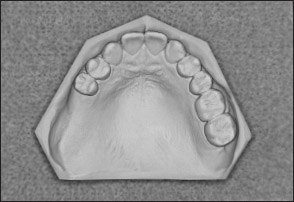

• Kennedy Class I arch: Characterized by bilateral edentulous areas located posterior to the remaining natural teeth (Figs 1-11 and 1-12).

Fig 1-11 Maxillary Kennedy Class I arch.